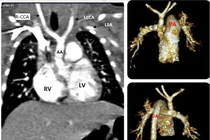

Kỹ thuật đặt stent graft được coi là một bước đột phá của nền y học hiện đại, giúp đem lại những hiệu quả vượt trội so với các phương pháp phẫu thuật truyền thống để điều trị bệnh lý động mạch chủ.

(khoahocdoisong.vn) - Gián đoạn quai động mạch chủ là một dị tật tim bẩm sinh cần được phát hiện sớm và phẫu thuật kịp thời nếu không bệnh dễ gây tử vong cho trẻ.

(khoahocdoisong.vn) - 70 – 80% lóc tách động mạch chủ (ĐMC) tử vong trong 2 tuần đầu. Có nhiều nguy cơ gây bệnh nhưng tăng huyết áp và tuổi là yếu tố thường gặp nhất.

(khoahocdoisong.vn) - Bệnh được coi là “thảm họa” trong các bệnh lý tim mạch, diễn biến rất nhanh, xử trí kịp thời tỷ lệ tử vong vẫn cao. Vậy phải phòng tránh bệnh này như thế nào?